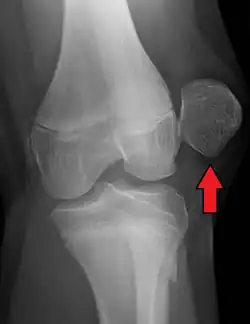

| X-ray showing a patellar dislocation, with the patella out to the side. | |

A patellar dislocation is a knee injury in which the patella (kneecap) slips out of its normal position.[5] Often the knee is partly bent, painful and swollen.[1][2] The patella is also often felt and seen out of place.[1] Complications may include a patella fracture or arthritis.[3]

A patellar dislocation typically occurs when the knee is straight and the lower leg is bent outwards when twisting.[1][2] Occasionally, it occurs when the knee is bent and the patella is struck directly.[1] Commonly associated sports include soccer, gymnastics, and ice hockey.[2] Dislocations nearly always occur away from the midline.[2] Diagnosis is typically based on symptoms and supported by X-rays.[2]